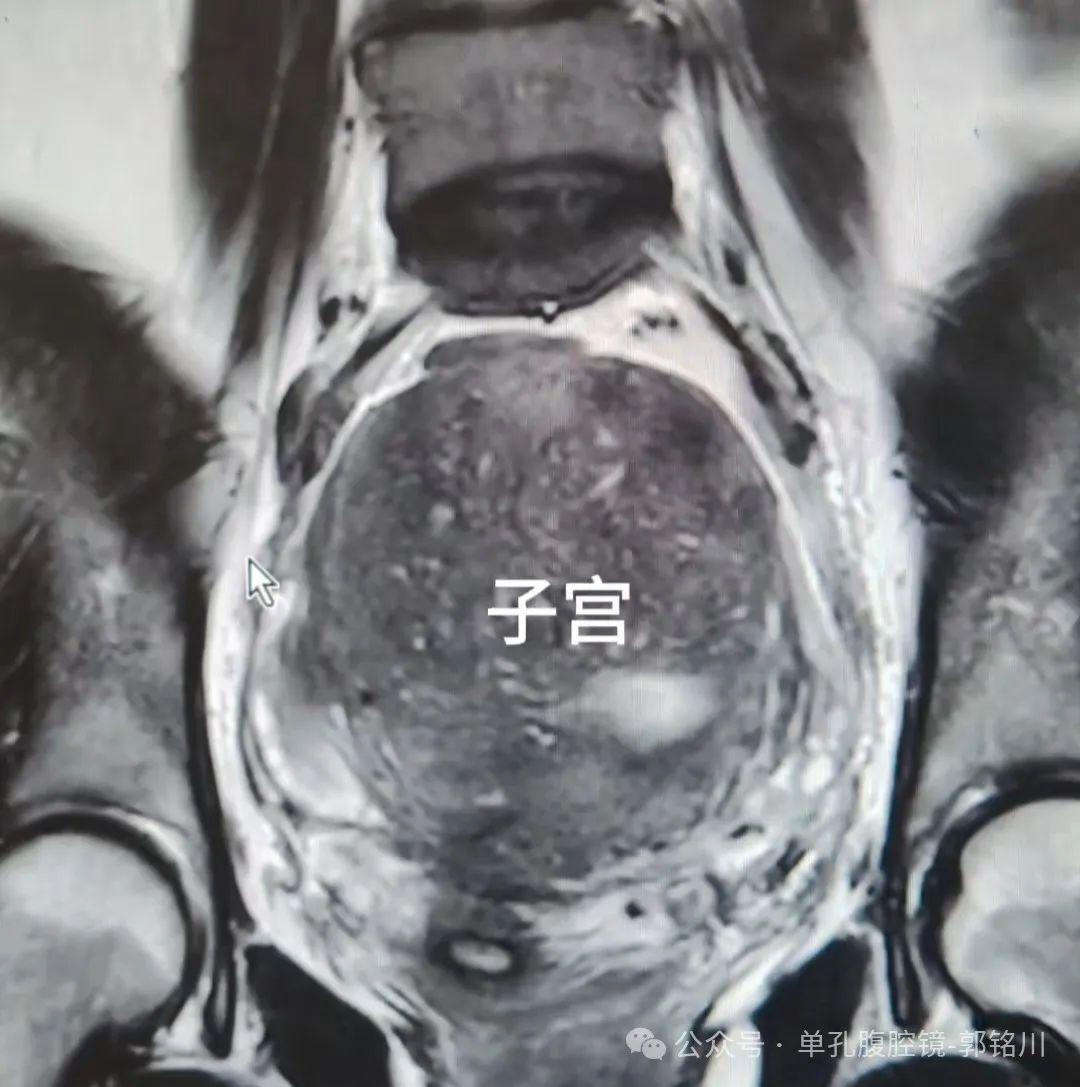

底下是术前影像相片

子宫腺肌症是一类以痛经、月过程多,和子宫迟缓增大为证据的子宫内膜异位症。患者会跟着子宫的不休变大症状越来越重!

该患者是饱受子宫腺肌症困扰的女性,出血、贫血、痛经,履历了漫长的保守调整,最终下定决心来切除子宫。

手术切除的标本重达430g,平常子宫惟有50~70g!